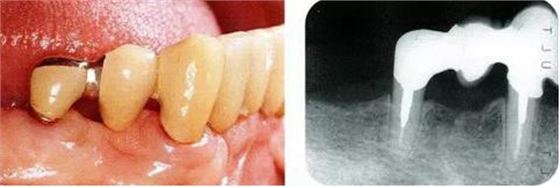

圖17-1 ( 左 ),2 ( 右 )▲右下4近中9mm的骨緣下缺損,兩側(cè)全口橋體修復(fù),但是這顆患牙保留的情況下會(huì)影響牙列的維持,鄰接牙的骨水平在較高的位置,拔牙后可以獲得平坦的骨水平。即使是右下4嘗試再生療法,假說(shuō)可以100%的成功,右下3遠(yuǎn)中骨水平也會(huì)形成3mm以上的臺(tái)階。而且再生治療也需要患者登上1年半以上的時(shí)間。所以最終選擇拔牙的處理。